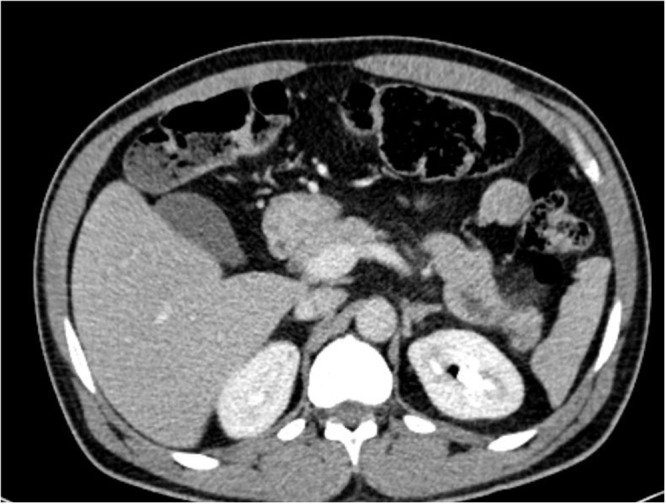

Case presentation: A 45-year-old male with a history of poorly controlled T2DM and hyperlipidemia presented with a 24-hour history of severe epigastric abdominal pain, fatigue, and vomiting. Clinical examination revealed diffuse abdominal tenderness, tachypnea, tachycardia, and a habitus consistent with central obesity. His BMI was 33.2 kg/m². Initial laboratory findings included seriously elevated triglycerides (1509 mg/dL), lipase (83 U/L), and amylase (161 U/L), along with hyperglycemia (465mg/dL). Abdominal computed tomography (CT) scan showed peripancreatic fatty stranding, consistent with early acute pancreatitis, as well as a fatty liver and a focal hypodense lesion in the right lobe. Treatment included intravenous insulin, dextrose, and potassium infusions to reduce triglyceride levels, analgesics, intravenous fluids for electrolyte imbalances, and thromboprophylaxis with enoxaparin.